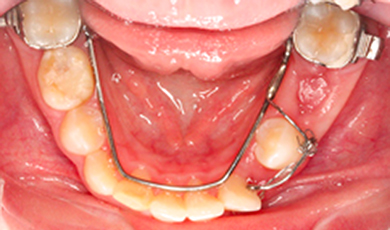

Início do tracionamento

Inicio do tracionamento ortodontico apos exposicao cirurgica ainda com a presenca de dentes deciduos, utilizando um arco lingual de apoio.